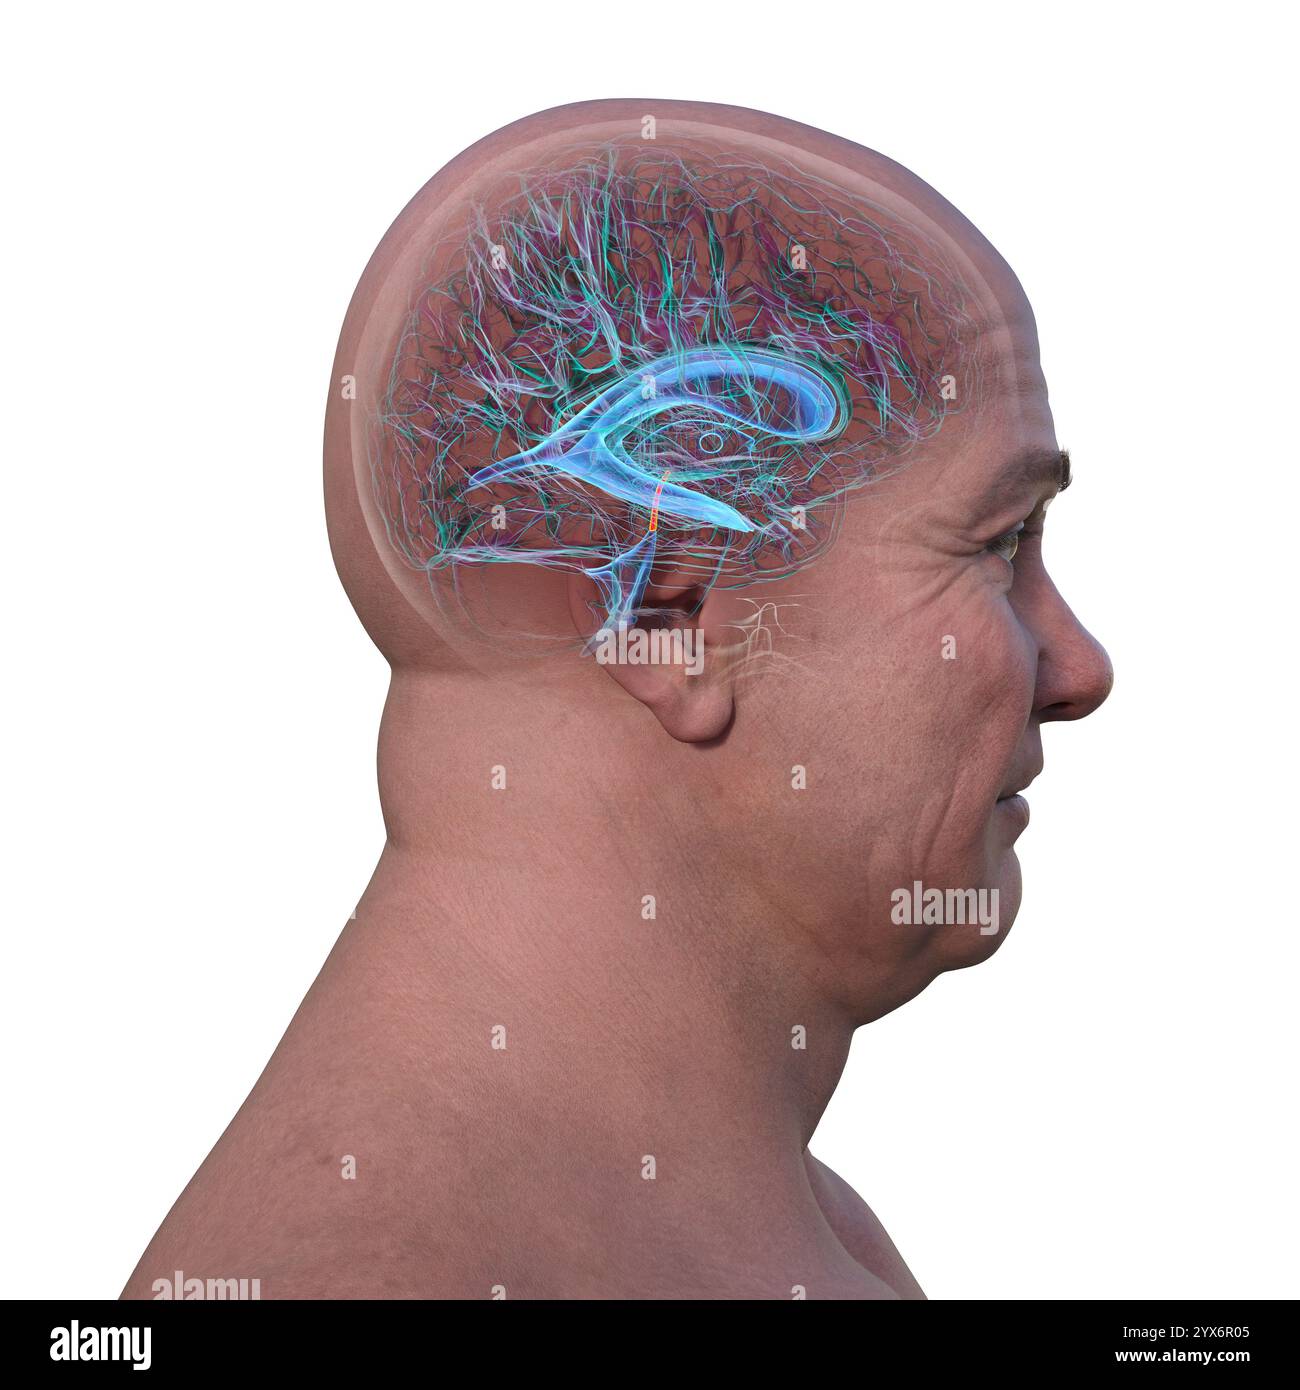

RF3C7H8A6–Abbildung des Gehirns mit hervorgehobenem Aquädukt (rot) und ventrikulärem System (blau), Darstellung des Liquorflusses.

RF3C7H8A3–Abbildung des Gehirns mit hervorgehobenem Aquädukt (rot) und ventrikulärem System (blau), Darstellung des Liquorflusses.

RF2YX6R0N–Computerdarstellung des menschlichen Gehirns mit orangefarbenem Aquädukt und grünem Ventrikelsystem, die den Liquorfluss (CSF) zeigen.

RF2YX6R0K–Computerdarstellung des menschlichen Gehirns mit orangefarbenem Aquädukt und grünem Ventrikelsystem, die den Liquorfluss (CSF) zeigen.

RF2YX6R02–Computerdarstellung des menschlichen Gehirns mit orangefarbenem Aquädukt und grünem Ventrikelsystem, die den Liquorfluss (CSF) zeigen.

RF2YX6R05–Computerdarstellung des menschlichen Gehirns mit orangefarbenem Aquädukt und grünem Ventrikelsystem, die den Liquorfluss (CSF) zeigen.

RF2YX6R0G–Computerdarstellung des menschlichen Gehirns mit orangefarbenem Aquädukt und grünem Ventrikelsystem, die den Liquorfluss (CSF) zeigen.

RF2YYB746–Computerdarstellung des menschlichen Gehirns mit orangefarbenem Aquädukt und grünem Ventrikelsystem mit Liquorfluss.

RF2YYB74E–Computerdarstellung des menschlichen Gehirns mit orangefarbenem Aquädukt und grünem Ventrikelsystem mit Liquorfluss.

RF2YYB751–Computerdarstellung des cerebralen Aquädukts (orange), eines schmalen Kanals im Mittelhirn, der den dritten und vierten Ventrikel verbindet und den Liquorfluss erleichtert.

RF2YYB74X–Computerdarstellung des cerebralen Aquädukts (orange), eines schmalen Kanals im Mittelhirn, der den dritten und vierten Ventrikel verbindet und den Liquorfluss erleichtert.

RF2YYB75A–Computerdarstellung des cerebralen Aquädukts (orange), eines schmalen Kanals im Mittelhirn, der den dritten und vierten Ventrikel verbindet und den Liquorfluss erleichtert.

RF2YYB741–Computerdarstellung des menschlichen Gehirns mit orangefarbenem Aquädukt und grünem Ventrikelsystem mit Liquorfluss.

RF2YYB742–Computerdarstellung des menschlichen Gehirns mit orangefarbenem Aquädukt und grünem Ventrikelsystem mit Liquorfluss.

RF2YYB754–Computerdarstellung des cerebralen Aquädukts (orange), eines schmalen Kanals im Mittelhirn, der den dritten und vierten Ventrikel verbindet und den Liquorfluss erleichtert.

RF2YYB75B–Computerdarstellung des cerebralen Aquädukts (orange), eines schmalen Kanals im Mittelhirn, der den dritten und vierten Ventrikel verbindet und den Liquorfluss erleichtert.

RF2YYB759–Computerdarstellung des cerebralen Aquädukts (orange), eines schmalen Kanals im Mittelhirn, der den dritten und vierten Ventrikel verbindet und den Liquorfluss erleichtert.

RF2YYB755–Computerdarstellung des cerebralen Aquädukts (orange), eines schmalen Kanals im Mittelhirn, der den dritten und vierten Ventrikel verbindet und den Liquorfluss erleichtert. Rückansicht.

RF2YYB752–Computerdarstellung des cerebralen Aquädukts (orange), eines schmalen Kanals im Mittelhirn, der den dritten und vierten Ventrikel verbindet und den Liquorfluss erleichtert. Rückansicht.

RF2YYB75E–Computerdarstellung des cerebralen Aquädukts (orange), eines schmalen Kanals im Mittelhirn, der den dritten und vierten Ventrikel verbindet und den Liquorfluss erleichtert. Ansicht von unten.